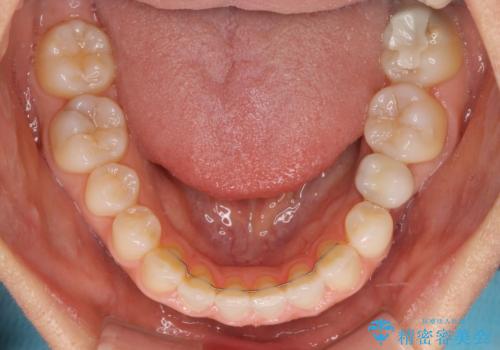

下顎前歯は空隙歯列弓であったので、アンカースクリューとワイヤー装置を用いてスペースを閉じていくこととし、上顎前歯は矯正治療用の仮歯に置き換えた上で、仮歯の大きさを削って小さくしながら、上下前歯部の部分矯正を行うこととしました。

矯正治療後は、仮歯とした上顎前歯をオールセラミッククラウンにて補綴治療を行うこととしました。

日本と海外を拠点に仕事をされていらっしゃるため、数ヶ月治療があいてしまうことがあり、期間はかかりましたが、2年間で望み通りの前歯に仕上げることができました。